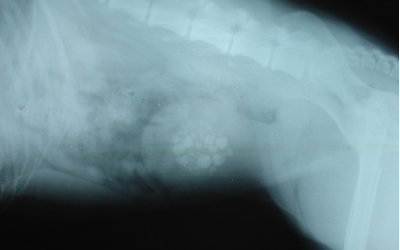

Rentgenološki pregled mokraćnog mjehura

Kamenci su ( uroliti – porijeklom iz bubrega ili cistoliti – porijeklom iz mokraćnog mjehura ) stjenolike tvorbe, sastavljene od organskih i neorganskih minerala, koje  se razvijaju i nastaju u mokraćnom mjehuru. Raspon u veličini se kreće od većih pojedinačnih kamenaca do kolekcija malih kamenaca poput zrna pijeska ili šljunka. Obično se radi o mješavini oba oblika.

Veliki kamenci djeluju poput sigurnosnog ventila uzrokujći djelimičnu ili povremenu obstrukciju (začep ) vrata mokraćnog mjehura, mjesto za koje se veže uretra.

Manji kamenci s protokom urina dospijevaju u uretru gdje mogu zastati I uzrokovati obstrukciju. Ukoliko se obstrukcija ne olakša mokraćni mjehur može pući.